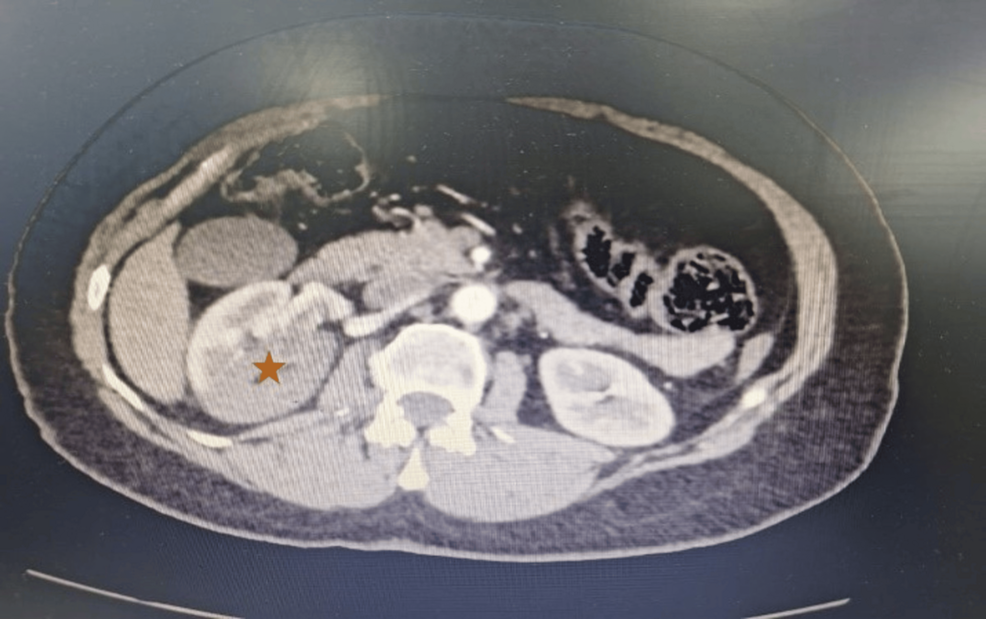

imaging findings that Confirm Renal Infarction

- CT angiography (CTA) – non‑contrast phase: wedge‑shaped hypodense area in the superior pole of the left kidney, lacking contrast enhancement.

- CTA – arterial phase: abrupt cut‑off of a segmental branch of the left renal artery, confirming arterial occlusion.

CTA remains the gold standard for ARI diagnosis, offering a sensitivity > 95 % and allowing simultaneous assessment for alternative causes such as stones or masses (2).

- Elevated LDH and a wedge‑shaped hypodense area on CTA are pathognomonic imaging signs.